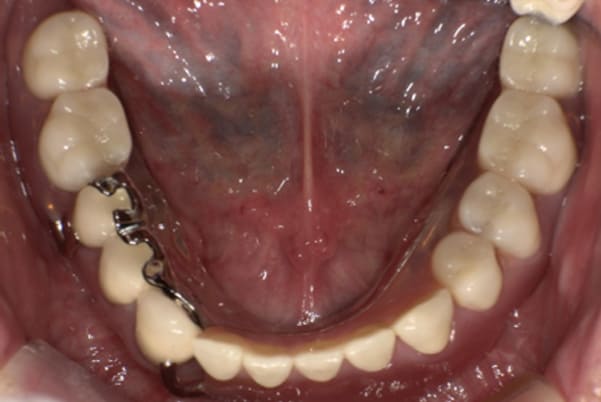

下顎治療前

下顎治療後

治療前の入れ歯の奥歯は、治療後の義歯と比較しても分かるように、歯が削れ平らになった状態です。

これにより奥歯のかみ合わせは低くなり、前歯のみが強くあたり、かみ合わせにより上の前歯大きな負担がかかっていたことにより、上の前歯が折れたことが考えられます。

治療前は、奥歯が下がり、かみ合わせが乱れています。適切な入れ歯はそのままのかみ合わせで義歯を作るのではなく治療後のように、前歯から奥歯までのラインが真っすぐ揃った、かみ合わせの面を適切に付与し、よく咬め、残りの歯に負担がかからないかみ合わせとしました。